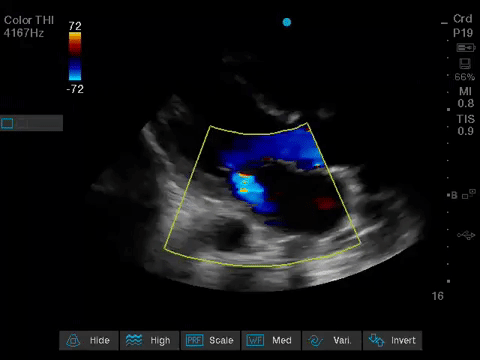

Before giving their clinical interpretation of the LUS findings, the POCUS team also scanned the heart and vasculature to obtain a more complete picture.

A comprehensive echocardiogram confirmed the POCUS findings. Her depressed LVEF was thought to be due to either septic cardiomyopathy or chemotherapy toxicity.